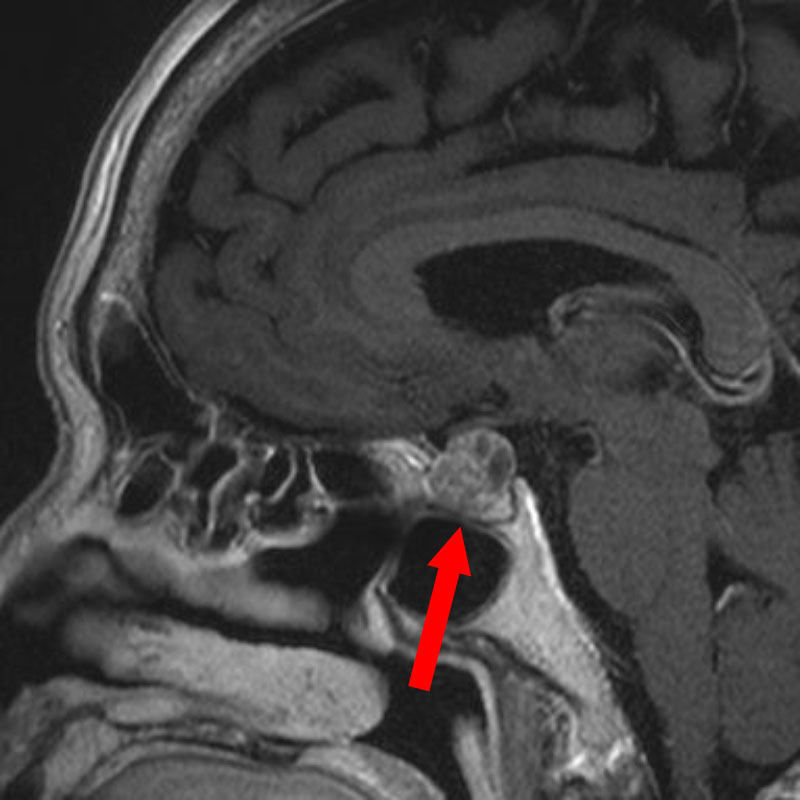

694

'25年11月

90代

頭蓋咽頭腫

頭蓋内腫瘍摘出術

No.’25_96 手術前1

No.’25_96 手術前2